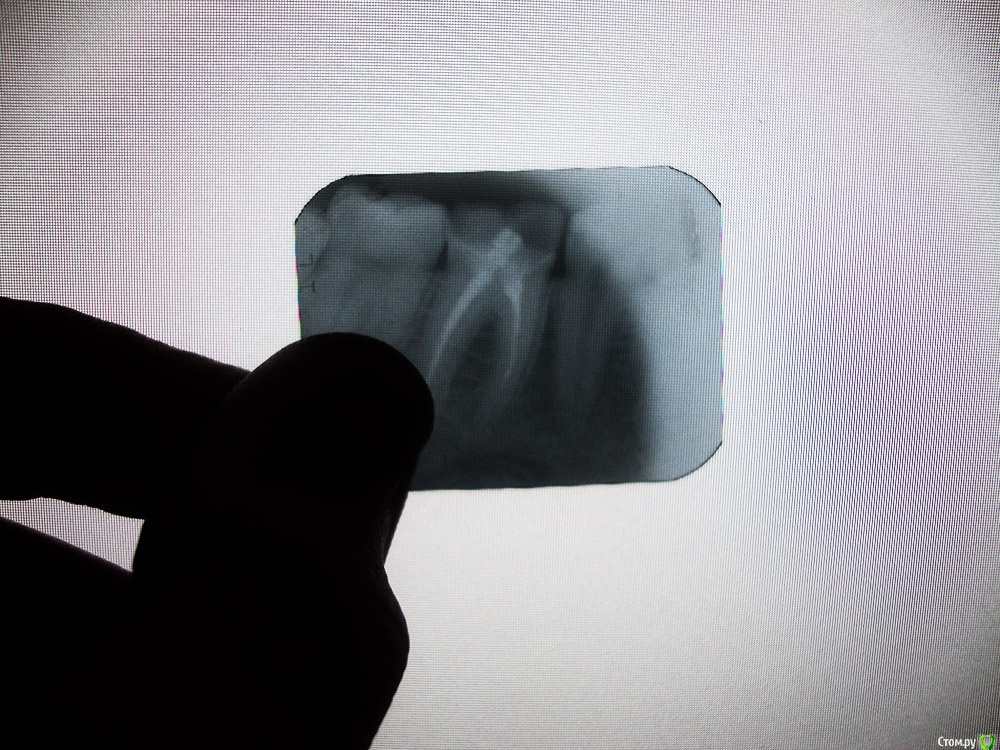

horreodor Опубликовано 26 марта, 2016 Поделиться Опубликовано 26 марта, 2016 снимок не качественный. как я обычно рекомендую, делать 3д, что бы более точно сказать даигноз и шансы на успех повторного эндодонтического лечения. дексаметазон в десну и сказали пить «Нимесил» скорее всего не изменять ситуацию. в лучшем случае приведут к временной ремиссии.по данным снимкам можно сказать что каналы запломбированы не до конца, поэтому скорее всего за 7 лет это и привело к переодонтиту. пломба не обычная, а волшебная видимо по этому поводу могу сказать что пломба и штифт у вас скорее всего вполне обычные. тут можно предложить два варианта. сделать 3д, оценить шансы на перелечивание каналов, после перелечивания каналов, делать нормальную вкладку и коронку. или удалять и имплантат. Ссылка на комментарий

St. Опубликовано 26 марта, 2016 Поделиться Опубликовано 26 марта, 2016 Про необычную пломбу повеселили Ещё вопрос : точно по ощущению этот зуб, а не соседние какие-нибудь или противоположные? Доктор во время визита на остальные зубы смотрел?И если есть панорамный снимок - выкладывайте.Если точно беспокоит этот зуб, то лучше его разобрать. По снимку видно плохо, но штифт и пломбу можно достать, дальше оценить что осталось от зуба и если всё нормально перелечить каналы. Дальше вкладка и корона, как Вам уже написали выше. 1 Ссылка на комментарий